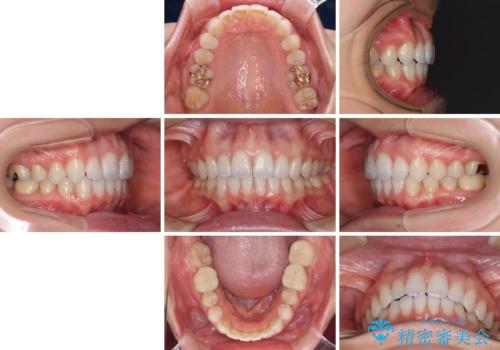

- 奥歯の虫歯と前歯のデコボコや突出感を気にして来院された患者様です。

上顎歯列が、下顎に対して前方にありましたが、口元に出っ歯の印象がなかったため、親知らずを抜歯した上で、上顎歯列全体を後方に移動させることとしました。

矯正治療後は、奥歯の虫歯や銀歯を補綴・修復治療することとしました。

上顎歯列を下顎に対して4mmほど移動させる必要があったため、治療は長期化することが予想されましたが、患者様にはこちらの期待以上にゴムかけなどに協力いただき、補綴治療も含めて2年強で終えることができました。